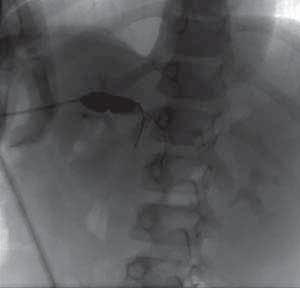

Rycina 119.5.